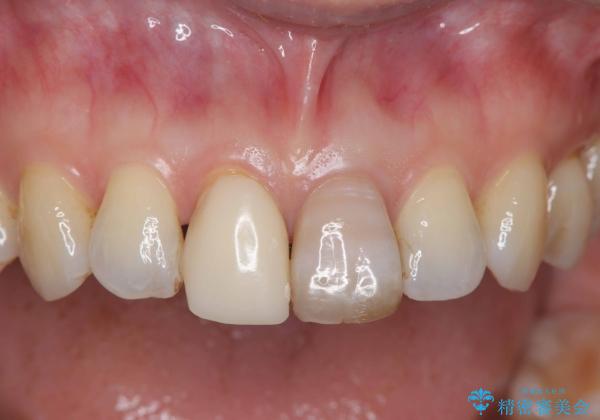

精密根管治療を行い、その後オールセラミッククラウンで審美的に修復しています。あわせてホワイトニングとエアフローによるクリーニングも行い、自然で美しい仕上がりとなりました。

他院で抜歯と診断された歯が、当院での治療により2本とも保存でき、見た目もきれいに仕上がりました。患者様にも大変ご満足いただけました。